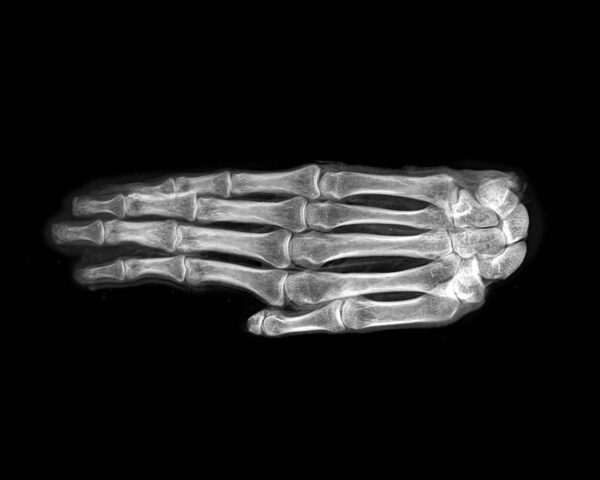

Description

| ITEM | Mummified hand with X-Ray |

| MATERIAL | Bone and linen |

| CULTURE | Egyptian |

| PERIOD | Late Period, 664 – 332 B.C |

| DIMENSIONS | 200 mm x 73 mm x 30 mm |

| CONDITION | Good condition. Includes digital copy of the X-ray test |

| PROVENANCE | Ex French private collection, Auvergne, acquired before 1980s |